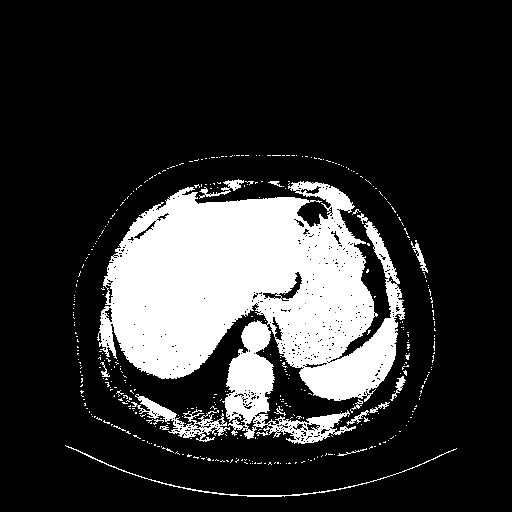

Original VENOUS CT scan

Full window (WL 1023.5, WW 4095 β†’ Low βˆ’1024, High +3071)

Actual HU range: [-1024.0, 3071.0]